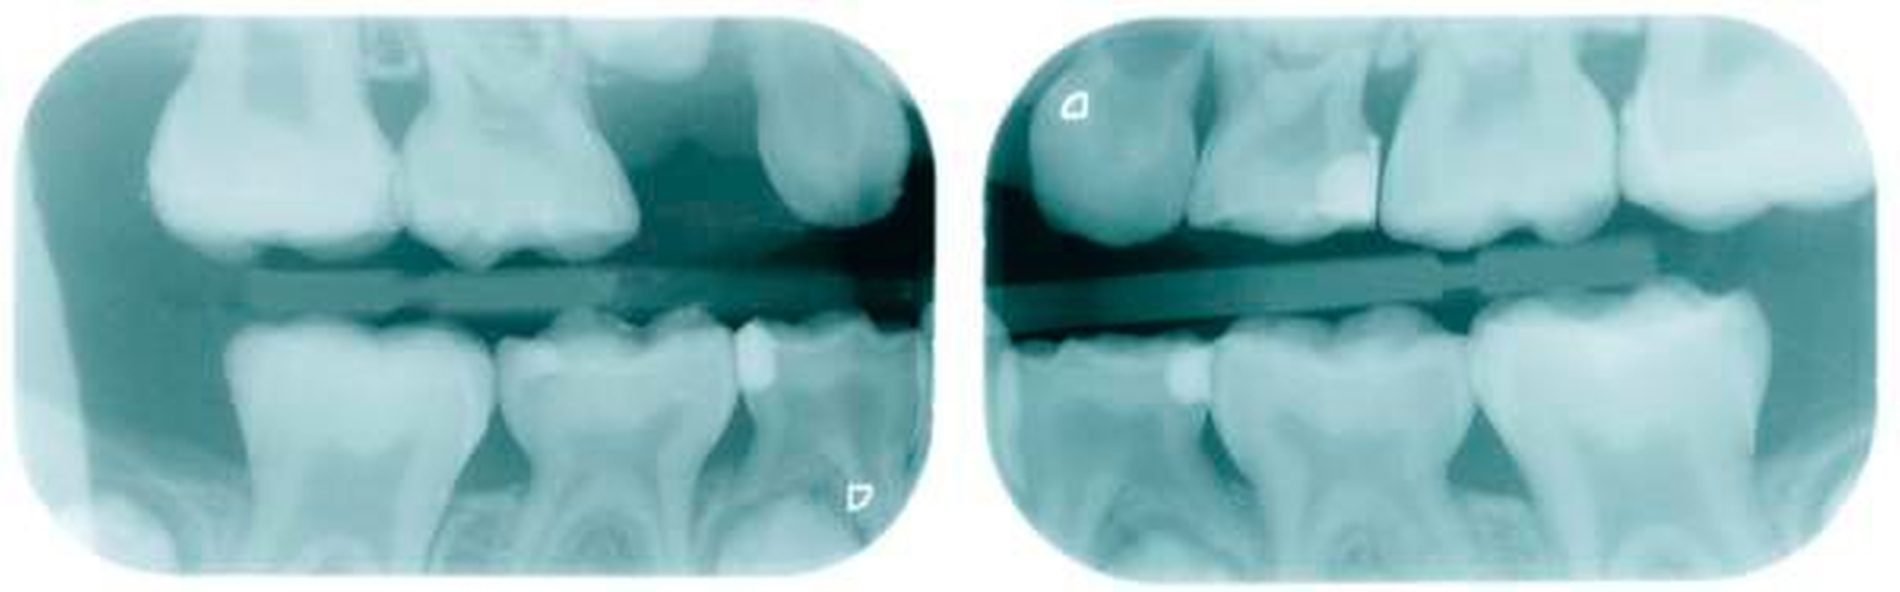

Leider ist die Präparation der Sechsjahrmolaren oft zeitraubender und geht meist mit erheblichem Substanzverlust einher. Nach versuchter schonender tangentialer Präparation mesial und distal sowie Reduktion der Höhe um circa 1,5 mm wird die entsprechende Kronengröße ausgewählt. Diese kann noch durch Kürzen oder Biegen des Randes individualisiert werden. Wichtig ist es, vor dem definitiven Einsetzen der Kronen den korrekten Sitz mittels Röntgenbild zu überprüfen. Bedingt durch das Fehlen eines basalen Schmelzwulstes lässt sich die Konfektionskrone trotz eines elastischen Federrandes auf dem konisch beschliffenen Zahn nur schwer fixieren. Störungen der Okklusion sind die Norm (noch unproblematisch im beginnenden Wechselgebiss), ein exakter Randschluss ist praktisch nicht zu erreichen. Insbesondere interdental, am Übergang zwischen Krone und Zahn, sind in jedem Fall Retentionsnischen vorhanden, die die Ansammlung von Plaque begünstigen. Folgeproblem ist Sekundärkaries und eine dauerhafte Irritation des marginalen Parodontiums. Verbleiben die Kronen über das 15. Lebensjahr hinaus im Mund, muss mit zum Teil erheblichem Knochenabbau gerechnet werden!

Befund:Abgesehen von einer insgesamt verzögerten körperlichen und dentalen Entwicklung aufgrund der Vorerkrankung, zeigte sich der extraorale Befund unauffällig, der intraorale Befund zeigte ein Wechselgebiss. An allen ersten Milchmolaren konnte Approximalkaries festgestellt werden. Alle Sechsjahrmolaren sowie die Schneidezähne im Ober- und im Unterkiefer waren, unterschiedlich ausgeprägt, von MIH betroffen. Das Zähneputzen und Essen wurde zunehmend zur Belastung aufgrund der Schmerzempfindlichkeit. Außerdem wurde Substanzverlust an Zahn 46 bemerkt (Abbildungen 9 und 10).

Gemeinsam wurde entschieden, dass die nicht so schmerzempfindlichen Frontzähne zunächst so belassen und gegebenenfalls später, wenn die optimale Zahnstellung erreicht ist, mit Füllungen oder Veneers versorgt werden. Die Zähne 16, 26 und 46 sollten mit Keramikkronen versorgt werden (Abbildungen 11 bis 13). Der weniger stark betroffene Zahn 36 sollte, wenn möglich, mit einer Kunststofffüllung versorgt werden. Eine mögliche spätere Extraktionstherapie je nach Engstand oder auch anstelle einer gegebenenfalls notwendigen Weisheitszahnentfernung wurde abgeklärt. Hinzu kam eine Füllungstherapie für die Zähne 64, 74 und 84. Der Zahn 54 wurde extrahiert, da die Wurzelresorption für eine Pulpotomie schon zu fortgeschritten war.